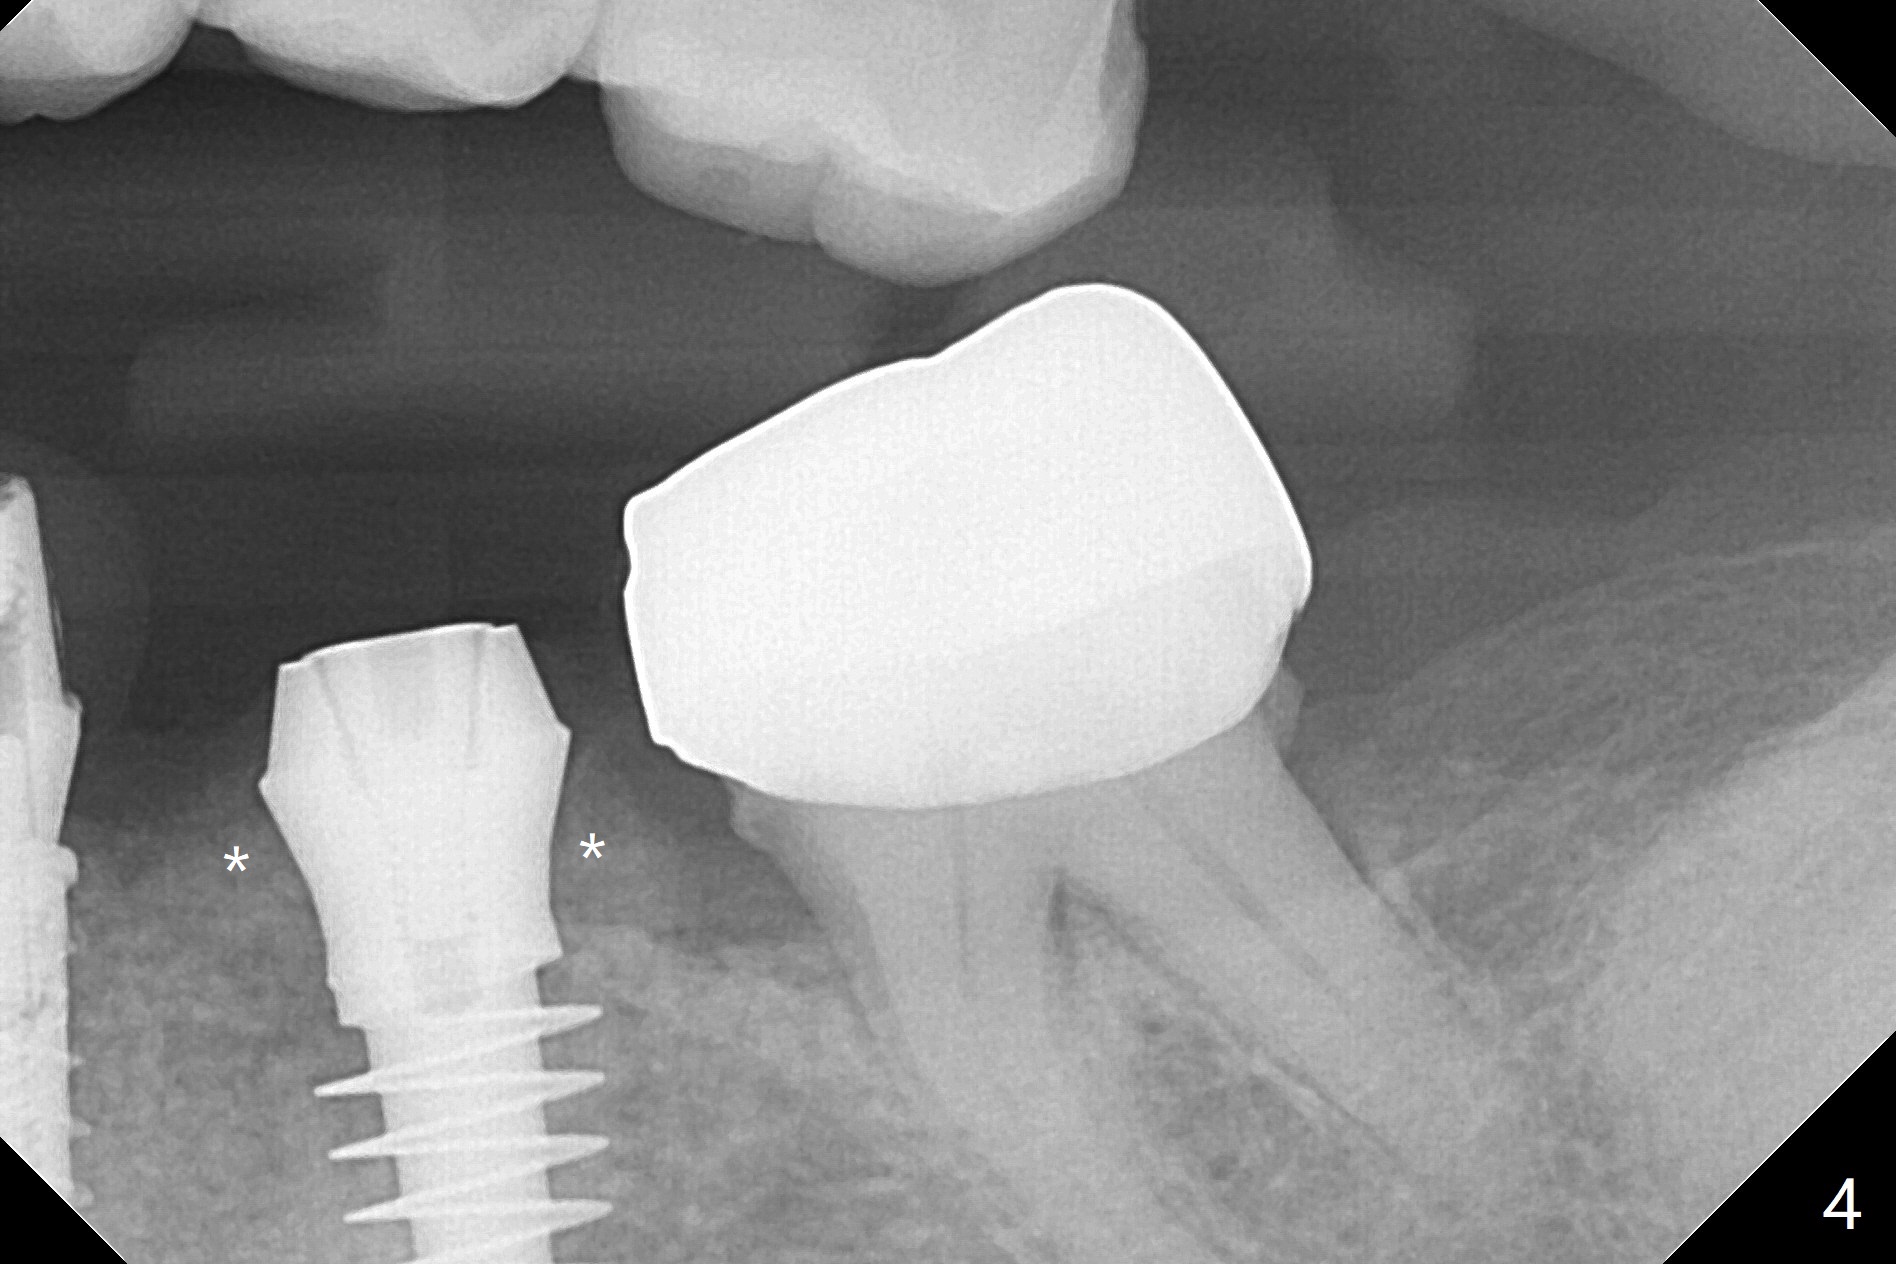

In fact the ridge at #19 is wide (Fig.1); there is enough bone to place a 5 mm implant (Fig.2 (5 mm implant positioner)). The gingiva is 3 mm in thickness. After use of Marking Drill, 5.3 mm Magic Drill (MD) for 9 mm and 4.8 mm MD for ~10 mm, a 5.5x9(3) mm Magicore is placed with primary stability, but too deep. When the implant is reversed, stability loses. After the autogenous bone from bone core is placed in the osteotomy, stability restores to a certain degree (Fig.3); there is no occlusal clearance when a 4.3x3 mm solid abutment is placed. Vera graft is placed around the implant (Fig.4 *) and a healing screw is placed (Fig.4,5).

There is no bone loss at #20 or 19 six and 3 months postop, respectively (Fig.6,7). After placing and trimming a 4.3x3 mm Magicore solid abutment, impression is taken (Fig.8). After cementation for #19 and 20 crowns, the crown of #20 is removed for cement removal; attention is paid to cement removal around the crown at #19. In fact, the removal is ineffective with the crown of #20 is reseated and retightened (Fig.9 >). Repeated removal proves to be futile (Fig.10 >). The most effective method will be to take X-ray immediately after #20 crown removal and reseating without torque so that it will be easier to remove the remaining cement if needed. It may be ok in term of hygiene, since proximal brush is used daily. While the crowns at #18 and 19 are being redone because of food impaction, the tooth #18 needs RCT; the Magicore seems to have no bone loss 4 months post cementation (Fig.11). CBCT shows that the Magicore seems to have been placed in the middle of the crest 7 months post cementation (Fig.12 (B: buccal)). The gingiva at #19 is apparently healthy 8 months post cementation. The crown at #19 is recemented 10.5 months post cementation (Fig.13).